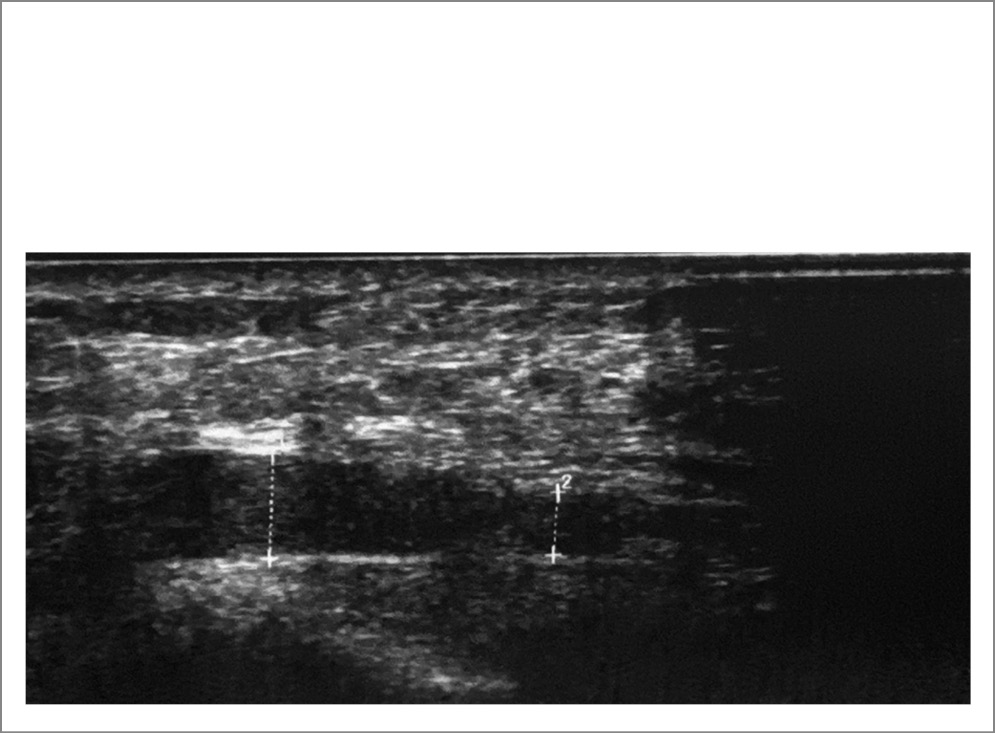

УЗИ от 06.09.2022: локтевой нерв в области средней трети плеча 7 мм2 (норма 6,55–-2,12 мм2) и нижней трети плеча 15 мм2; на предплечье: в области нижней трети 4 мм2, в средней – 4 мм2; на запястье – 3 мм2 (норма на уровне локтевого сгибателя запястья 5,91–-1,77, на запястье – 4,09+1,38 мм2); овальной формы с четким гиперэхогенным контуром и внутренней гетерогенной, упорядоченной структурой. Расположение типичное. В канале и по выходу из канала контур неровный, толщина 1,8×1,9×1,4 мм, эхогенность снижена, нарушена дифференциация, по внутреннему контуру локально, на протяжении 4 мм на глубину 0,5 мм – гиперэхогенный участок в поперечном срезе, создающий иллюзию удвоения, площадь поперечного сечения в этом участке 8 мм2, нерв уплощен. Заключение: посттравматическая нейропатия левого локтевого нерва в кубитальном канале. УЗ-картина выраженной компрессии левого локтевого нерва на уровне кубитального канала (рис. 1–3).

Рис. 2. УЗ-картина при кубитальном туннельном синдроме. Утолщенный локтевой нерв при продольном сканировании со сниженной высотой в дистальном сегменте канала и отечно-воспалительными изменениями проксимальнее места сдавления.